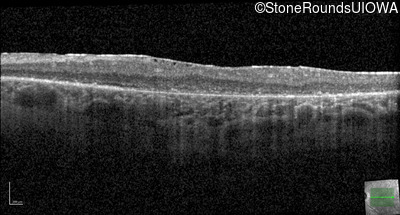

Optical Coherence Tomography - Left - 20/125 -1

Exemplar / OCT Stack